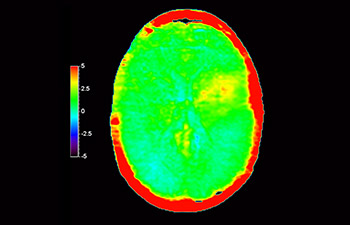

Lesión cerebral

con 3D APT